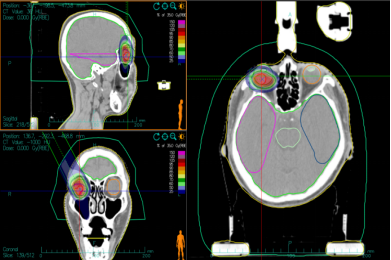

病例3:女性,59岁,右眼眶ACC术后。于2023年4月四川大学华西医院行“右眼眶内肿物切除+眼眶修补术”,术后病检提示:ACC。术后1月就诊于我院,目前患者眼睑闭合、右眼外转和下转明显受限。经过对患者全面检查和评估,患者于2023年6月12日接受CIRT治疗,一程处方剂量为PTVboost:15Gy(RBE)/5fx。二程处方剂量为PTV:54Gy(RBE)/18fx,肿瘤总剂量达到69Gy(RBE)/23fx,剂量分布见图7。CIRT和VMAT计划在均满足处方要求的前提下,在轴位图像剂量分布的典型对比,周围正常组织CIRT计划较VMAT计划低剂量照射范围明显缩小,见图8。CIRT治疗前、后通过影像学资料对比疗效,根据RECIST1.1肿瘤疗效评价标准评估患者疗效,疗效达部分缓解(PR),见图9。CIRT治疗期间及治疗后1月内,患者出现1级放射性皮肤损伤,未观察到大于2级的不良反应。截至2024年7月,目前患者带瘤生存,继续长期随访。

图7 眼眶ACC患者离子治疗剂量分布图

Figure 7 Ion therapy dose distribution in orbital ACC patients

Note: Figure 7A: One course CIRT dose distribution. Figure 7B: Two course CIRT dose distribution

图8 眼眶ACC患者VMAT计划及碳离子计划剂量分布图

Figure 8 VMAT plan and carbon ion plan dose distribution in orbital ACC patients

Note: Figure 8A: VMAT plan dose distribution n orbital ACC patients. Figure 8B: Carbon ion plan dose distribution n orbital ACC patients.